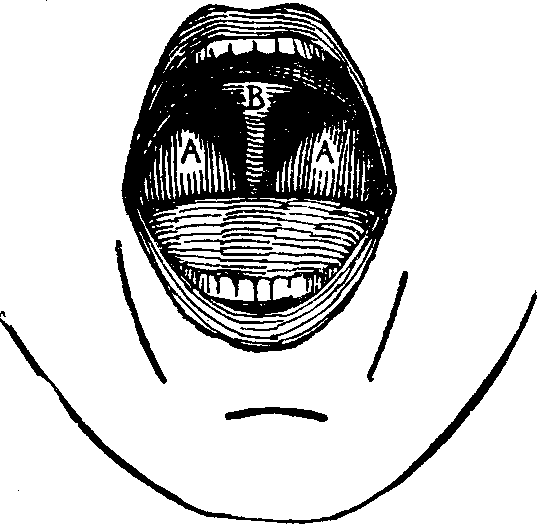

The Tongue is a flat oval organ, the base of which is attached to the os hyoides, while the apex, the most sensitive part of the body, is free. Its surface is covered with a membrane, which, at the sides and lower part, is continuous with the lining of the mouth. On the lower surface of the tongue, this membrane is thin and smooth, but on the upper side it is covered with numerous papillæ, which, in structure, are similar to the sensitive papillæ of the skin.